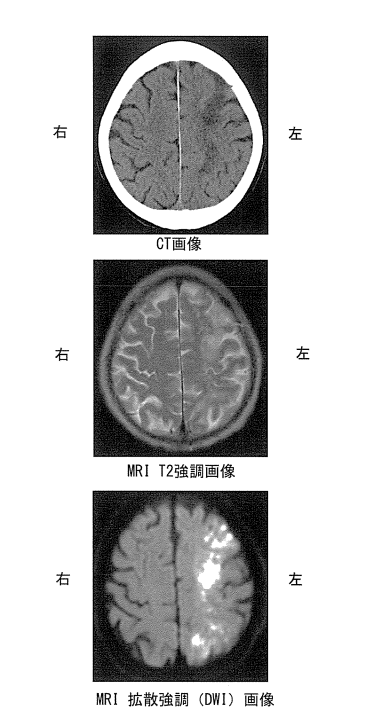

問題15 頭部画像を下に示す。

考えられる診断はどれか。

1.脳梗塞

2.脳出血

3.外傷性脳損傷

4.くも膜下出血

解答1

核磁気共鳴画像法(MRI)とは、核磁気共鳴現象を利用して生体内の内部の情報を画像にする方法である。治療前にがんの有無や広がり、他の臓器への転移がないかを調べたり、治療の効果を判定したり、治療後の再発がないかを確認するなど、さまざまな目的で行われる精密検査である。

①拡散強調像(DWI):超急性期(発症後1~3時間)

②FLAIR像:発症後3~6時頃

③T2強調像:発症後3~6時頃

④T1強調像の順である。

1.〇 正しい。脳梗塞が考えられる診断である。なぜなら、新しい脳梗塞は、CTではやや低吸収域、MRI拡散強調画像では鮮明な高信号城として描出されるため。

・CTでは壊死した脳組織が周囲よりX線を吸収しにくくなるため、やや低吸収域として描出される。

・MRIの拡散強調画像(DWI)は、細胞レベルでの水分子の拡散運動の変化を捉える画像であり、新しい脳梗塞では細胞がむくんで水分子の動きが制限されるため、鮮明な高信号域として描出される。

2.× 脳出血の場合、頭部単純CTで「実質内の高吸収域(白く見える)」として見える。

3.× 外傷性脳損傷で、出血を伴う場合(硬膜外血腫、硬膜下血腫、脳挫傷、外傷性くも膜下出血など)、頭部単純CTで「実質内の高吸収域(白く見える)」として見える。

4.× くも膜下出血の場合、頭部単純CTで「くも膜下腔の高吸収域(白く見える)」として見える。